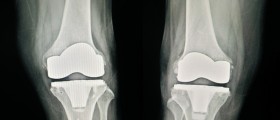

This operation is also known as hip arthroplasty. It includes the removal of the damaged joint and its replacement with an artificial one. This artificial joint is a prosthesis, and it comprises a socket and a ball component. The prosthesis is made of specific material which cannot be rejected by the body. It is also resistant to corrosion and degradation.